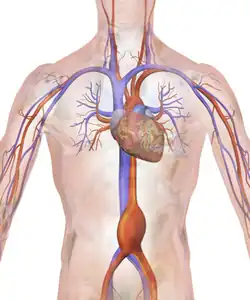

An aneurysm is an outward bulging, likened to a bubble or balloon, caused by a localized, abnormal, weak spot on a blood vessel wall.[1] Aneurysms may be a result of a hereditary condition or an acquired disease. Aneurysms can also be a nidus (starting point) for clot formation (thrombosis) and embolization. As an aneurysm increases in size, the risk of rupture increases, which could lead to uncontrolled bleeding.[2] Although they may occur in any blood vessel, particularly lethal examples include aneurysms of the circle of Willis in the brain, aortic aneurysms affecting the thoracic aorta, and abdominal aortic aneurysms. Aneurysms can arise in the heart itself following a heart attack, including both ventricular and atrial septal aneurysms. There are congenital atrial septal aneurysms, a rare heart defect.

- The aorta, namely aortic aneurysms including thoracic aortic aneurysms and abdominal aortic aneurysms.[9]

Endovascular coiling was introduced by Italian neurosurgeon Guido Guglielmi at UCLA in 1989. It consists of passing a catheter into the femoral artery in the groin, through the aorta, into the brain arteries, and finally into the aneurysm itself. Platinum coils initiate a clotting reaction within the aneurysm that, if successful, fills the aneurysm dome and prevents its rupture.[42] A flow diverter can be used, but risks complications.[43]

For aneurysms in the aorta, arms, legs, or head, the weakened section of the vessel may be replaced by a bypass graft that is sutured at the vascular stumps. Instead of sewing, the graft tube ends, made rigid and expandable by nitinol wireframe, can be easily inserted in its reduced diameter into the vascular stumps and then expanded up to the most appropriate diameter and permanently fixed there by external ligature.[44][45] New devices were recently developed to substitute the external ligature by expandable ring allowing use in acute ascending aorta dissection, providing airtight (i.e. not dependent on the coagulation integrity), easy and quick anastomosis extended to the arch concavity[46][47][48] Less invasive endovascular techniques allow covered metallic stent grafts to be inserted through the arteries of the leg and deployed across the aneurysm.